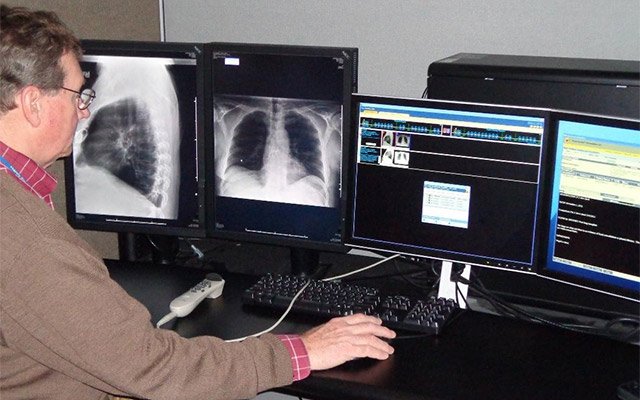

Telemedicine started in the 1960’s with radiologists working in Teleradiology. Evolving over the past two decades, all developments in information technologies, the digitalization and networking made big impacts. Connecting patients and doctors is driving the industry.

With demographical change and the rise of medical competence centres, providing clinical healthcare is very specialized and professional, but also offers more and more challenges. People live longer and their mobility is decreasing. They can’t use cars on their own and public transportation is challenging for them – especially when in medical need. With the NEC InfinityBoard – our all-in-one meeting room solution – and a decent healthcare partner network, Sharp meets the special requirements of the healthcare industry. Not only is the NEC InfinityBoard meant to be part of the MDT Room to enhance collaborative working and get remote participants on board, but also the Sharp solution enhances collaboration and consultancy with operating surgeons.

With the digitalisation of Operating Rooms, the work of surgeons and the whole team around becomes more and more efficient. Not only can surgeries inside the OR be supported by visualisation on Large Format Displays, but also video streaming makes an impact. Sharp, together with Kramer AV, supports the connection of OR’s to the outside world!

Live surgery and telestration are important, especially in teaching hospitals. While the surgeon operates, a head camera is live-streaming images to a bigger audience. In this way, many student surgeons can participate.